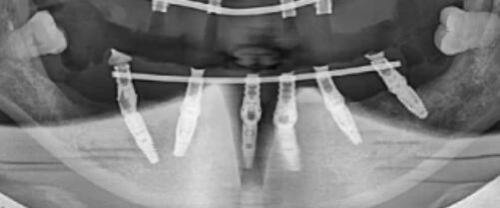

5. 我之前牙齿不好,需要种植牙。在惠水县人民医院,医生为我制定了合适的种植方案。术后牙齿修复得良好,外观和功能都和真牙一样。医院的口腔医生技术高超,服务态度也良好,让我有了一次愉快的就医体验。